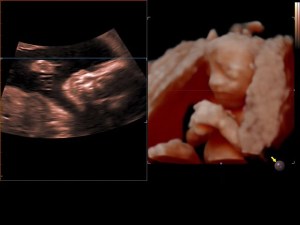

Mama en papa geven elkaar geen cadeautjes op Valentijn, maar dit jaar kozen we ervoor om deze feestdag toch een vrolijk kleurtje te geven door een extra bezoekje aan Cfor9. Je gelooft het echter misschien niet, maar jouw hoofdje was terug zo gedraaid dat we jou niet konden zien. Je staat precies even graag op de foto als jouw papa… niet dus (knipoog)!

Op 21 februari 2015 hadden we dan ook een nieuwe afspraak bij Sylvie. In plaats van jou nog eens te zien bij 32 weken zwangerschap konden we je nog even bewonderen bij 33 weken zwangerschap. Amai, wat ben je veranderd in vergelijking met de vorige keer. We zien echt dat je goed groeit. Vooral jouw bolle kaakjes vinden we zo schattig. Op het eerste zicht heb je trouwens de neus van de mama en de lipjes van de papa. Wat kijken we ernaar uit om jou te kunnen knuffelen!

Dit waren jammer genoeg wel de laatste 3D-beelden die we zullen kunnen zien van jou tijdens de zwangerschap. In het ziekenhuis maken ze enkel een 2D-echo en omdat je meer en meer met jouw hoofdje in mama’s bekken daalt zal Sylvie geen foto’s meer van jou kunnen maken.